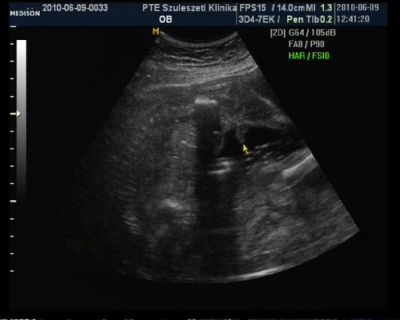

100%-ra ki lehet jelenteni hogy kislány

Mérete 23héttel egyezik ezért viszahivott 2 hét mulva csak egy mérésre hogy biztosak legyünk a terhességi korban. Szoktak ilyen 4D-n csinálni??

Szerintetek nem pofátlan dolog ha viszek neki desszertet meg egy kávét majd?Kaptam képet, dvd-dt és szakvéleményt. BDP 55mm (remélem jol emléxem mert a kociban van a papir reggle ugyis kell a mappám mert cukorvérvételre megyek ) A grammba biztos vagyok 536gramm

Aranyos husis, nagyo sokat szopizza az ujjacskáját! Készitettem képet nem épp a legjobb minőség, nem tudom mi van a géppel. De azért felteszem ide